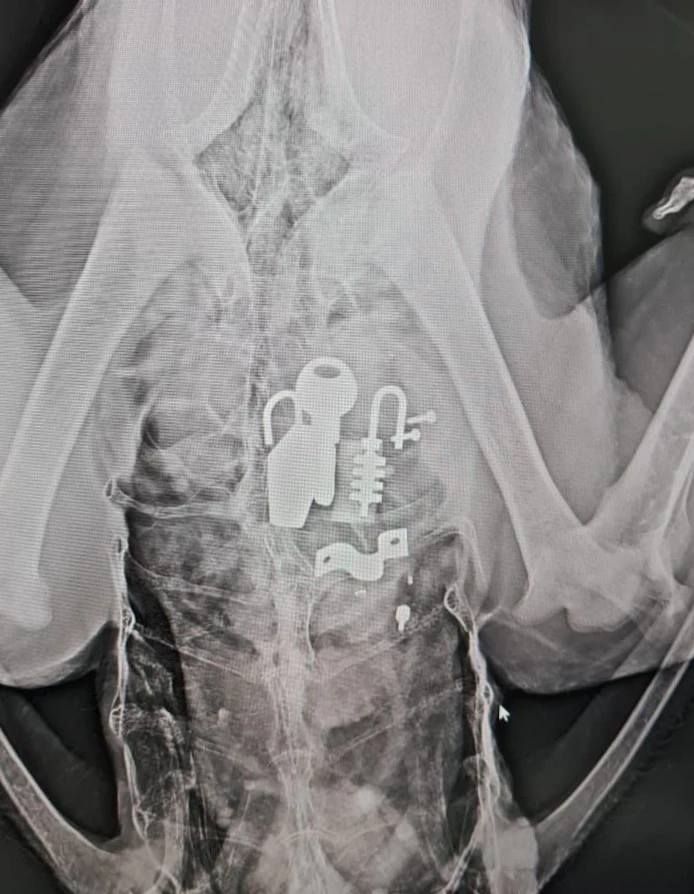

Görevliler 2 gün önce bakımını yapmak istedikleri nandu’nun hasta olduğunu fark etti. Veteriner hekime götürülen deve kuşunun midesinden kilit, anahtarlık ve çok sayıda aparat olduğu fark edildi. Ve nandu hemen ameliyata alındı. Ameliyatın ardından okula getirilen nandu hayatını kaybederken öldüğünü duyan okul çalışanları ve öğrenciler büyük üzüntü yaşadı.

Nandu’nun midesinden çakmak, değişik aparatlar ve kilit çıktığını belirten Şahbaz, “Elinde anahtar gördüğü zaman kovalıyordu, almadan bırakmazdı peşini. Çok üzgünüz, mutsuzuz, onun yeri dolmayacak, sevgisi de apayrıydı” diye konuştu.